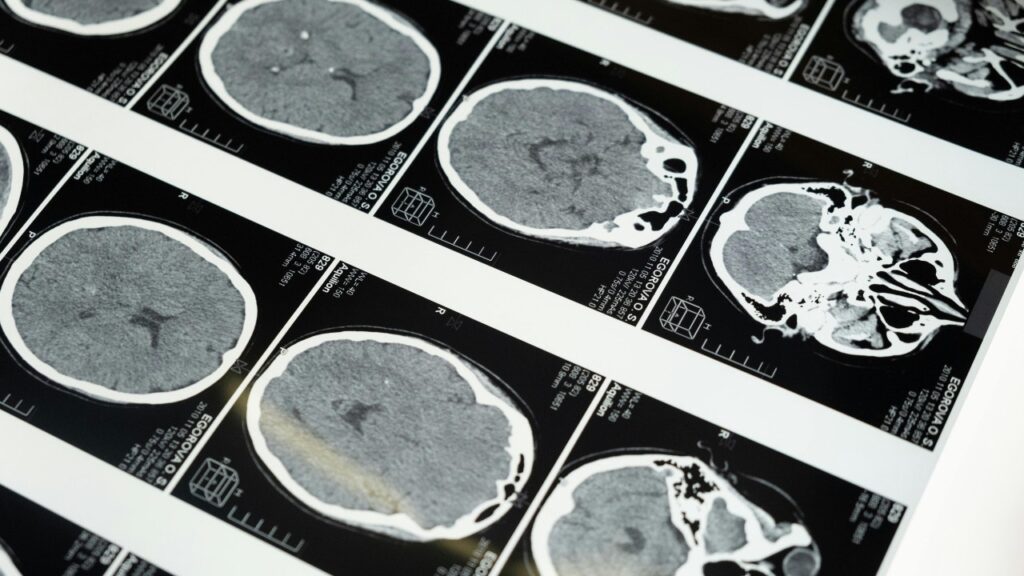

Brain imaging highlights the regions researchers study as companies explore noninvasive ultrasound brain-computer interface technology. (Kurt “CyberGuy” Knutsson)